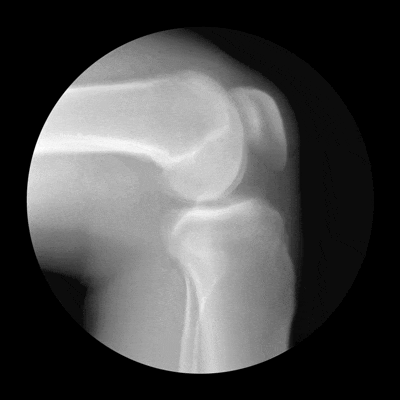

接诊的骨科陈东峰主任发现,温女士左膝关节轻度肿胀,关节活动受限,有疼痛症状,结合影像学表现,符合膝关节退行性骨关节病的典型特征,建议她入院治疗。

对于不同程度的骨关节病,医生会提供保守治疗(药物和物理治疗)、截骨术和全膝关节置换术等治疗办法。考虑到温女士的病变主要集中在前内侧区域,症状局限在膝关节内侧,没有明显的内外翻畸形,最终选择了部分膝关节置换术。

在麻醉科配合下,陈东峰主任手术团队清除了增生的滑膜组织,去除了骨赘,对关节进行了适当松解,术中发现关节面磨损严重,软骨下骨暴露,内侧半月板后角脱位。医生精心安置了人工关节假体,替代了已经损坏的关节面。

陈东峰主任介绍,骨关节炎是老年人的高发疾病,主要表现以关节软骨的磨损和破坏。随着年龄增长,关节软骨逐渐退化,软骨细胞合成功能下降,加上长期重复使用和负荷,关节边缘代偿性增生,导致软骨变薄、表面粗糙甚至碎裂。